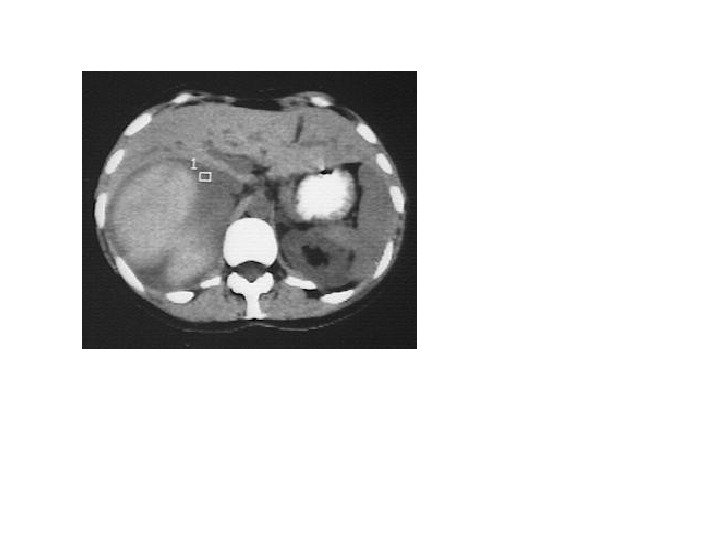

• В 10% случаев при феохромоцитоме компьютерная томография выявляет двустороннее поражение надпочечников. • Билатеральная феохромоцитома часто проявляется как незначительное увеличение надпочечников, с заметным повышением их васкуляризации. • Необходимо помнить, что феохромоцитома может иметь и вненадпочечниковую локализацию, располагаясь в паракавальных симпатических ганглиях, симпатических ганглиях средостения, ганглиях стенки мочевого пузыря.

• В 10% случаев при феохромоцитоме компьютерная томография выявляет двустороннее поражение надпочечников. • Билатеральная феохромоцитома часто проявляется как незначительное увеличение надпочечников, с заметным повышением их васкуляризации. • Необходимо помнить, что феохромоцитома может иметь и вненадпочечниковую локализацию, располагаясь в паракавальных симпатических ганглиях, симпатических ганглиях средостения, ганглиях стенки мочевого пузыря.